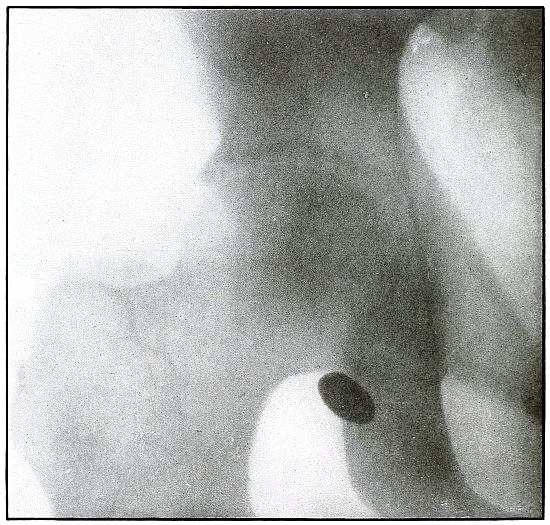

PELVIS.

Plate 46.

[Pg 103]

Rifle—Plate 46.

PELVIS.

Gunshot Wound of the Pelvis,

with Lodgment of the Missile in the Abdomen.

The course of the bullet was from behind forward, striking the crest

of the ilium, on which it was deflected, and spattering off some lead

fragments. The slight penetration indicates a velocity of extremely

long range and a striking energy lessened by ricochet.

The irregular outline of the shadow of the projectile shows its

deformity, and the blurred outline indicates intra-abdominal movement

with respiration.

While the missile, as revealed by its shadow, is not a shrapnel ball,

the distribution of lead particles is more suggestive of a shrapnel

than of a rifle projectile, and the ballistic conditions are more

characteristic of the former than of the latter.

There was no abdominal reaction; the invasion of the abdomen was

revealed by the radiograph.

The treatment in such cases is noninterference unless subsequent

developments furnish definite indications.